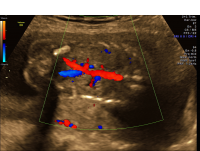

Unilateral renal agenesis color dopplers coronal

Unilateral renal agenesis may be associated with other anomalies of the urinary tract, intestinal tract, or heart, and may be an element of many syndromes. When identified, a detailed anatomical ultrasound and a specialized ultrasound focusing on the fetal heart (“echocardiogram”) should be performed to evaluate for coexisting anomalies. A consultation with a geneticist and discussion of genetic testing options are also recommended.

A pregnancy with isolated unilateral renal agenesis will be managed in much the same way as any other pregnancy.